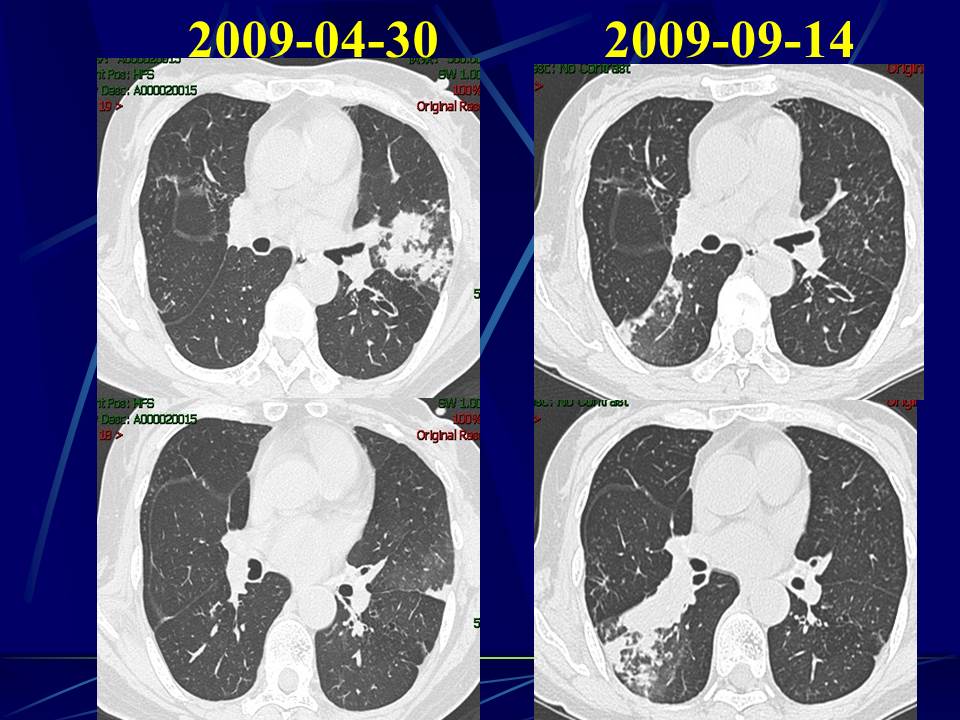

肺部真菌感染影像学分析